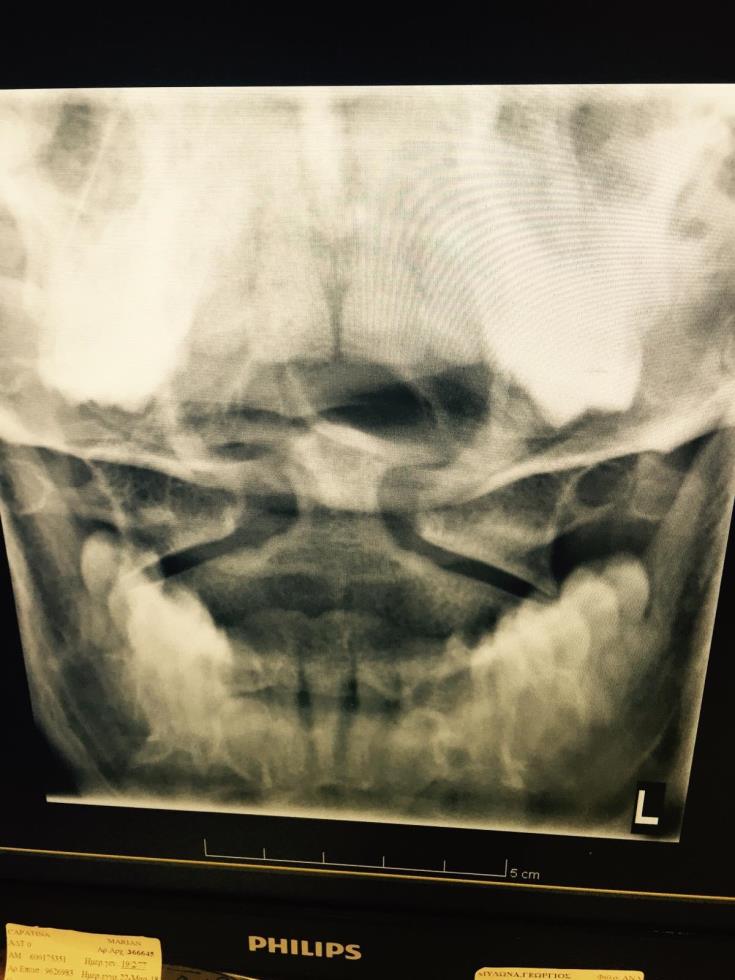

Στην τρίτη σελίδα, στην κατηγορία ΕΡΓΑΣΤΗΡΙΑΚΕΣ ΕΞΕΤΑΣΕΙΣ, προκύπτει ότι η ασθενής υποβλήθηκε σε Ακτινογραφίες και Αξονική τομογραφία, δίπλα από την οποία γράφει «head».

Από εκεί και πέρα, εντός του report επισυνάπτεται η εξέταση του θύματος από το ακτινολογικό τμήμα του νοσοκομείου, όπου καταγράφονται τα εξής:

- ΘΜΣΣ (Θωρακική Μοίρα Σπονδυλικής Στήλης)

- ΟΜΣΣ (Οσφυϊκή Μοίρα Σπονδυλικής Στήλης)

- ΑΜΣΣ (Αυχενική Μοίρα Σπονδυλικής Στήλης)

Πέραν του report, η πηγή επισυνάπτει ακτινογραφίες που λήφθηκαν, στις οποίες καταγράφεται το όνομα της ασθενούς, ημερομηνία και ώρα, στην βάση των οποίων φαίνεται καταγράφεται η πιο πάνω διάγνωση.

Επίσης, παραπέμπει και στις καταχωρήσεις που έγιναν στο Τμήμα Πρώτων Βοηθειών του Γενικού Νοσοκομείου Λευκωσίας, όπου καταγράφεται η επίσκεψη και διάφορα άλλα στοιχεία.